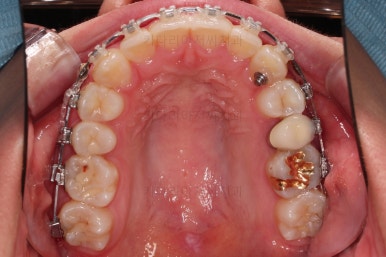

악궁확장을 먼저 시행합니다.

아랫니에 비해서 윗니의 악궁의 폭이 좁기 때문에 가로폭을 먼저 개선합니다.

Q. 미니스크류를 심고 악궁확장 해야 하나요?

저희 부산비대칭교정 키다리아저씨치과에서는 CT분석으로 악궁확장의 필요량, 필요 여부, 미니스크류를 이용해야 하는지 여부를 100%는 아니지만 높은 확률로 추정하여 시행합니다.

이번 환자분은 성인이긴 했지만 미니스크류 없는 일반 타입의 악궁확장장치로 시도하기로 했습니다.

악궁확장 이후, 유지단계 동안 확장의 유지에 필요한 치아를 제외하고는 브라켓을 부착하게 됩니다.

이번 환자분이 선택한 장치는 엠파워 클리어라고 하는 자가결찰 세라믹 장치인데요.